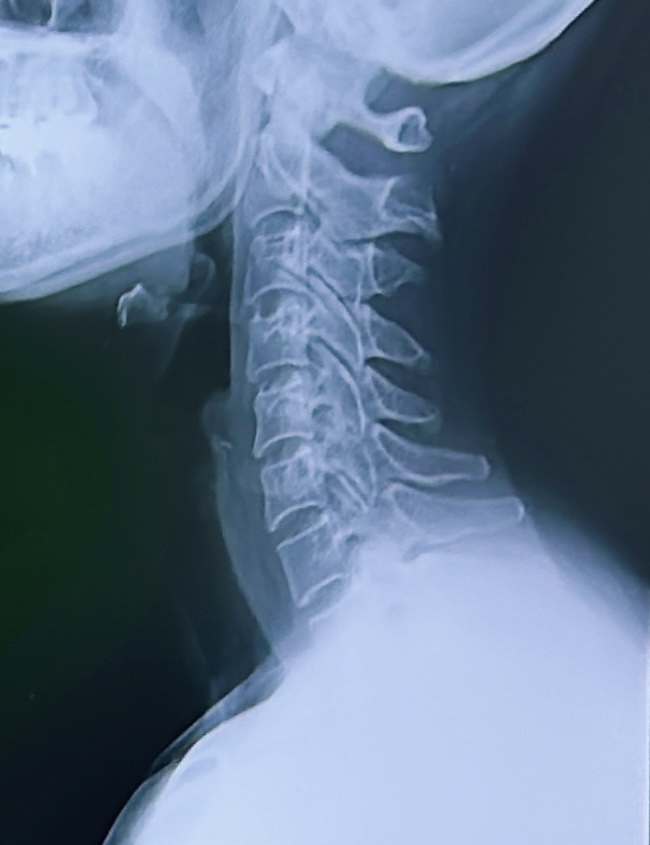

首から腰にかけてと左肩が痛くて病院でレントゲン撮ってもらったら左肩骨折の疑いとか言われる(後日MRIの結果骨折はなし、肩の打撲とむちうち)。電気治療とリハビリに通う。